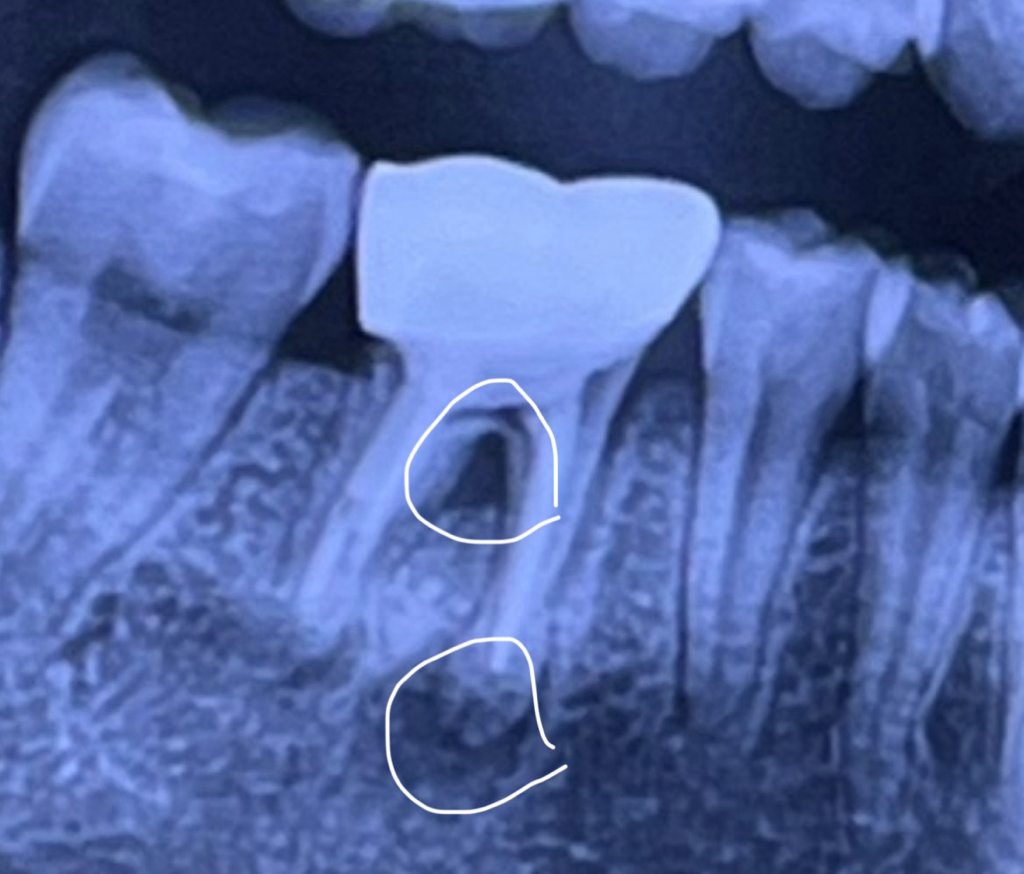

1. 치근단 절제술과 의도적 재식술 시행 가능하나 성공은 장담할 수 없습니다.

2. 말씀하신 치근 뿌리 사이 (치간이개) 도 뼈가 녹은 것이 맞습니다